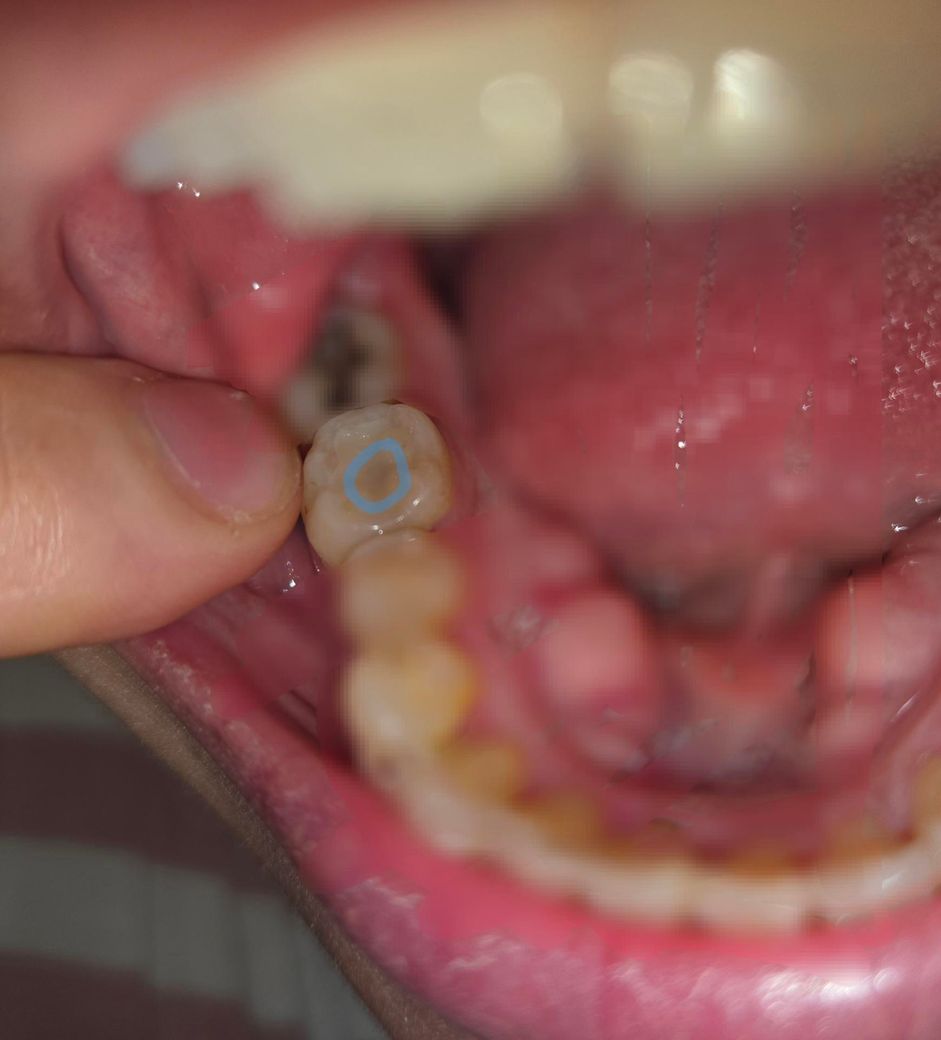

치과의사쌤들만 답변 부탁드려요ㅠ 어금니 세라믹으로 때웠는데 회색이 비쳐요

8년전에 어금니 세라믹 때웠던게 떨어져서 치과에갔더니

치아에 오염물이 많이 묻어있어서 긁어내야하므로

기존 세라믹을 그대로 붙이자니 사이즈가 안맞아서

새로 해야한다고 해서 세라믹 새로 붙였어요

충치는 아니였지만 기존 접착제가 녹은건지 오염물이 덕지덕지붙어있어서

오염물 부위는 갈아서 파냈습니다

파낸 자리에 새로운 세라믹을 맞춰서 다시 붙였는데

붙이자마자 치과에서 거울을 보니

어금니 중앙 한가운데에 (사진에 동그라미 해놓은 부분)이

회색처럼 보이길래

치과의사쌤한테 여기 왜 회색으로 보이냐 여쭤봤더니

그냥 문제없는거라고 하더라구요?

혹시 세라믹 아래에 충치가 있거나 오염물이 남아있어서 비치는거 아니냐 다시 여쭤봤는데

• 1번 째 사진